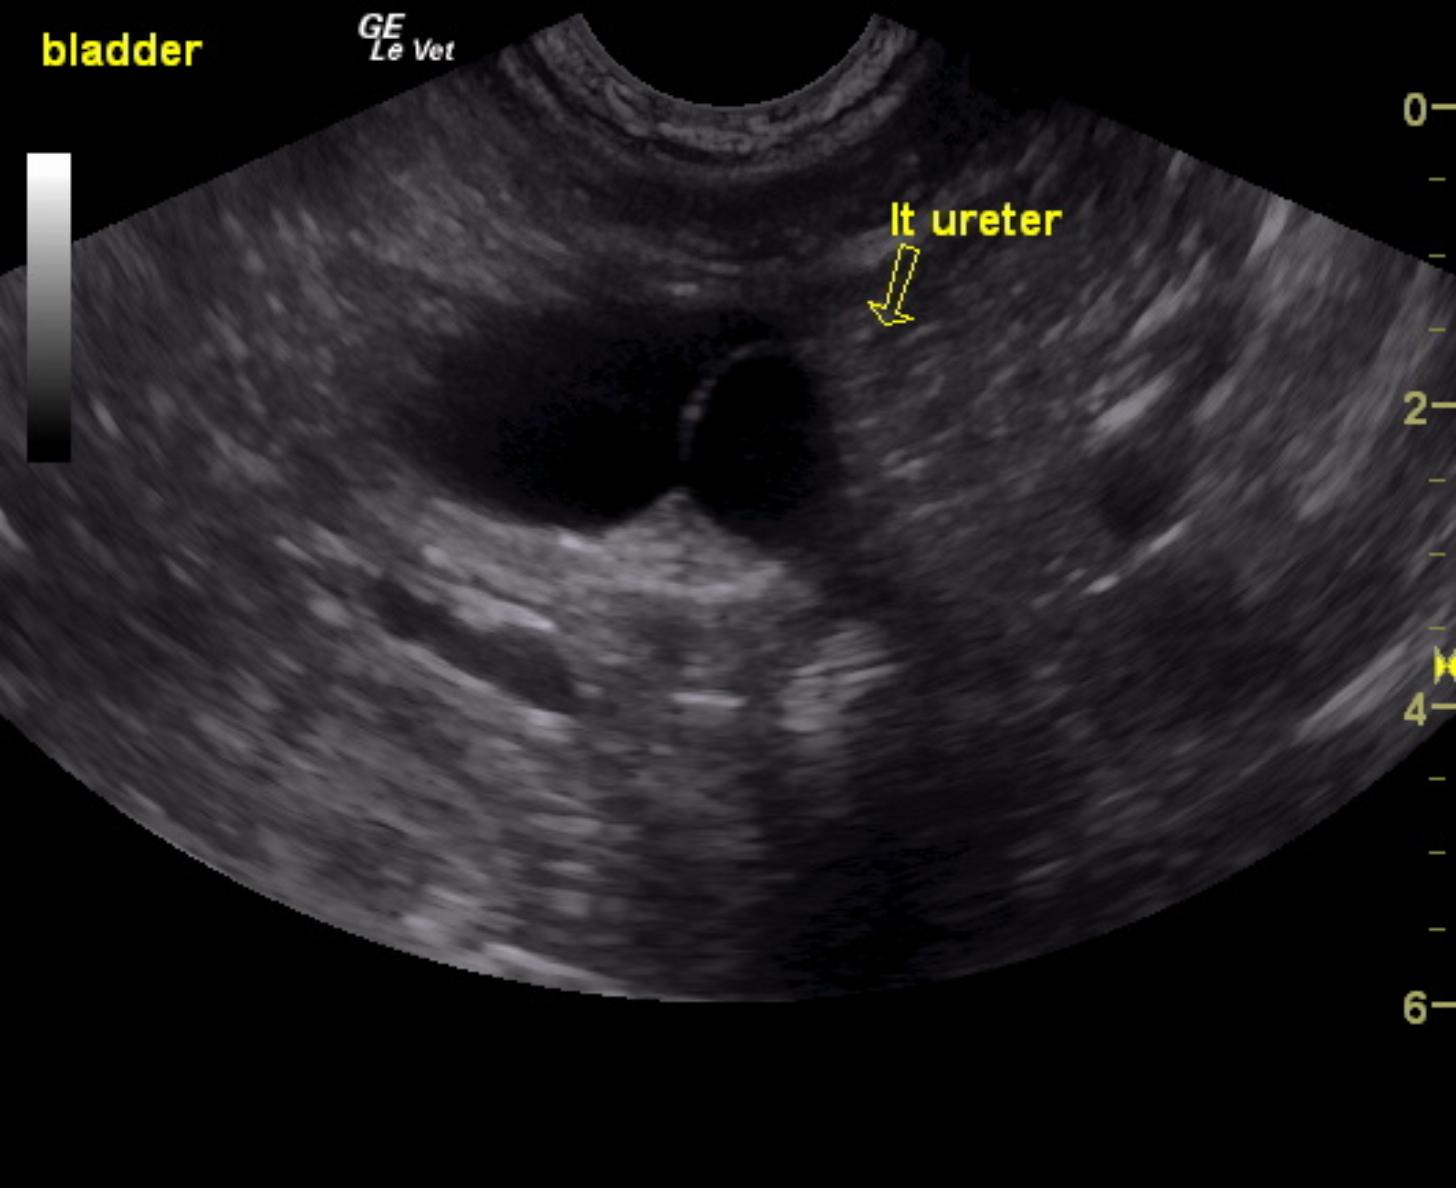

A 1-year-old neutered male Labrador retriever dog was presented for evaluation of urinary incontinence. Urine specific gravity was 1.039, and bloodwork was within reference range.